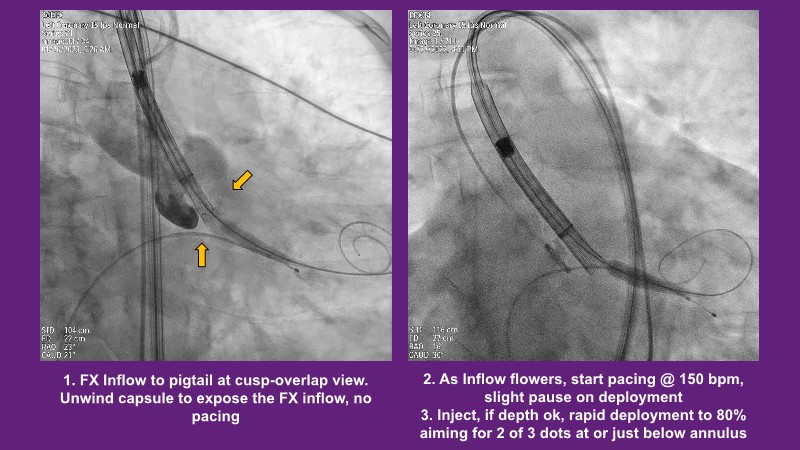

Don’t miss this PCR Tokyo Valves 2025 session replay, where leading experts share key techniques for simplifying and optimising TAVI procedures with the Evolut device. This session covers essential insights into safely performing procedures on patients with various anatomical types using the self-expandable valve, while emphasising the importance of long-term patient care and outcomes. Discover valuable strategies for surgical explantation of transcatheter aortic bioprostheses, coronary cannulation, and commissural alignment post-TAVR. Learn expert tips for streamlining procedures, such as semi-rapid pacing, using Dryseal long, and skipping pre-BAV to improve TAVI results. Watch now to stay ahead in the field!

- To understand simple procedure as semi-rapid pacing, using Dryseal long and skip pre-BAV